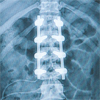

For all of our patients, a multi-disciplinary non-surgical approach is used. This approach allows the majority of our patients to improve without surgical intervention. When surgery is necessary, Dr. Bhatia's extensive training in state of the art techniques including minimally invasive surgery, endoscopic discectomy, percutaneous fusions, X-Stop lumbar stenosis treatment, Bone Morphogenetic Protein (BMP), and kyphoplasty help to cure his patients' problems with minimal recovery time and less discomfort than other methods.